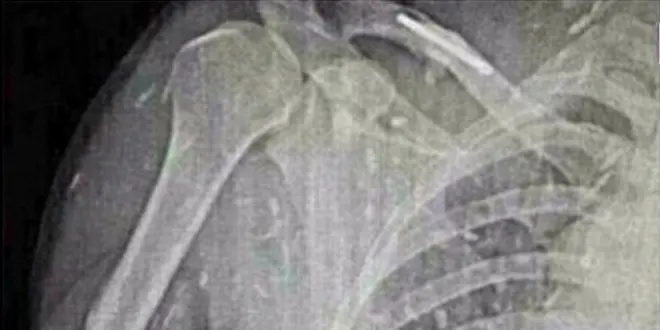

Les clichés versés à charge des sashimis sont, effectivement, très similaires à ceux d'articles scientifiques sur la cysticercose (voir ci-dessous).

Cliché extraits de : Extensive brain and muscular cysticercosis. T. Bejoy et K. Thamburaj, Neurology 2006; doi:10.1212/01.wnl.0000196639.85454.81